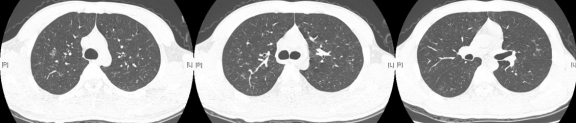

1、所谓急性HP,就是患者接触了较高水平的暴露,例如有患者喜欢饲养鸟类,尤其喜欢宠物鸽子,于是到交易市场去看,在这个过程中,可能出现了间断高水平暴露,于是一些易感个体就在很短的时间内(4到12小时)出现了流感样症状和呼吸道症状,而肺内则出现了一些磨玻璃影。

2、也有一些患者急性发作伴发热,劳力性呼吸困难、乏力和咳嗽,影像表现为小叶中央性的弥漫性的腺泡结节,称之为亚急性HP

3、还有些患者持续性低水平暴露,起病很隐匿,当我们发现时,已经出现了劳力性呼吸困难,干咳,体重减轻和乏力,而影像出现了既有磨玻璃影,也有肺纤维化的表现,称之为慢性HP

图:(从左至右)急性、亚急性、慢性